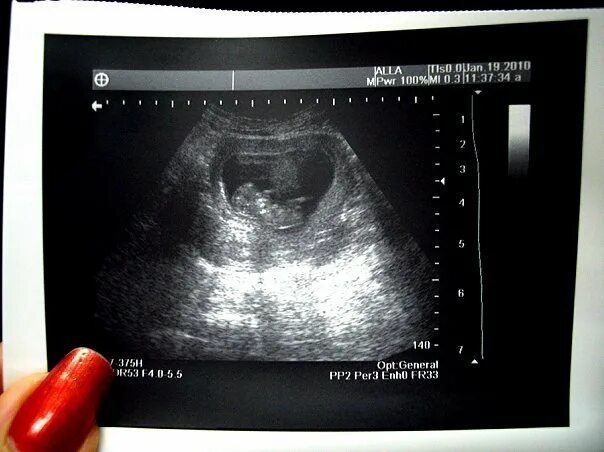

11 недель и 5 дней